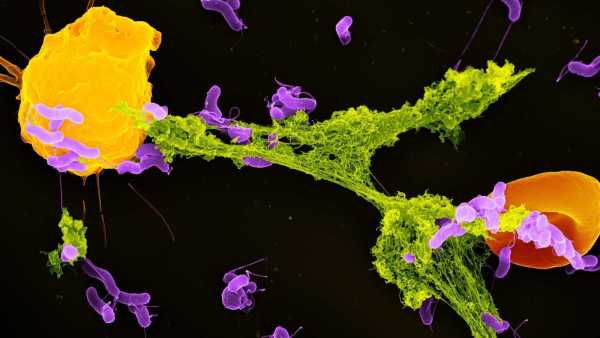

Щоб вивести більш гуманізованих мишей, дослідники спочатку вивели мишей, генетично модифікованих для ослаблення імунної системи. Коли мишам було приблизно 1-2 дні, команда ввела людські стовбурові клітини в серця тварин. Стовбурові клітини, які були вилучені та очищені з пуповинної крові, були здатні перетворитися на будь-який тип імунних клітин.

Потім серця тварин перекачували стовбурові клітини в м’яку губчасту тканину в кістках мишей, відому як кістковий мозок, де зазвичай виробляються імунні клітини. Оскільки миші мали імунодефіцит, людські стовбурові клітини могли легко закріпитися в кістковому мозку.

Після введення людського естрогену миші почали виробляти безліч людських імунних клітин. Серед них були Т-клітини, які безпосередньо атакують мікроби, та В-клітини, що виробляють антитіла, що знищують бактерії та допомагають позначити патогени для знищення.